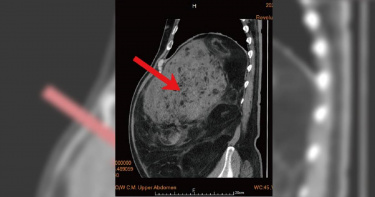

68歲男四肢瘦唯獨「肚腩大」 竟藏22公斤腫瘤「內臟都擠到移位」

68歲的楊先生身材高大壯碩,曾因心肌梗塞就醫撿回一命,後來積極透過飲食控制和運動減重,近五年來,楊先生減重有成四肢都瘦了,但瘦不下來的大肚腩對他而言十分困擾,經就醫檢查赫然發現,占據腹部的不是脂肪而是巨大腫瘤,就連肝臟及腸胃道都因腫瘤推擠而挪到腹腔左側。收治個案的馬偕紀念醫院泌尿科資深主治醫師邱文祥表示,楊先生罹患的是第三期惡性肉癌,經過腹部斷層掃描可見其腫瘤體積十分龐大,影響範圍從橫膈膜至下腔靜脈,腹部器官遭腫瘤推擠嚴重位移,右側腎臟也已被腫瘤包覆導致萎縮、下腔靜脈亦被嚴重壓迫。臨床上,惡性肉癌的病因不明,發生率是所有癌症的1%。邱文祥醫師表示,行醫40多年,也僅收治10多名患者,若能仔細而完整的切除惡性肉癌的影響範圍,患者5年存活率可達6至7成。由於病人的腫瘤體積龐大、侵犯範圍廣泛,為求謹慎,邱文祥醫師召集泌尿科、一般外科、心臟血管外科、胸腔外科等團隊,在擬定手術計畫後,協調各科別執行手術的醫師,以大隊接力賽的概念,掌握最少的時間與最有效的方式,接替為患者清除腹腔內的巨大腫瘤。最早進行手術的邱文祥醫師,以傳統開腹手術率先切除主要腹膜後腫瘤,並摘除右側萎縮腎臟,再由一般外科蔡崇鑫主任及朱敦邦醫師切除部分右側肝臟。由於病人的下腔靜脈主要血管已遭腫瘤包覆,腫瘤與主要血管間亦有許多小血管,因此再接著由心臟血管外科資深主治醫師李君儀協助分離包覆在血管上腫瘤,過程非常容易出血,也須立即將破掉的血管一一縫補,最後再由胸腔外科資深主治醫師詹梅麟與林哲弘醫師修補右側橫膈膜,才算是大功完成。一般外科蔡崇鑫主任對此手術印象深刻,他說:「因為患者的肝臟大移位,與人體解剖位置都不相同,下腔靜脈亦被腫瘤嚴重壓迫、非常不容易察覺位置,切除部分肝臟的手術過程只要稍有不慎就可能造成大出血,所幸外科團隊互相補位提醒,才能順利完成手術。」心臟血管外科資深主治醫師李君儀表示,在他參與的部分,最重要的關鍵在於處理腫瘤與血管之間的沾黏,因為腫瘤是整個包覆著大血管,而且和大血管之間有很多小血管相連,因此分離腫瘤並縫合血管的過程,花了不少時間。這也是他前所未見的大型腫瘤,所幸團隊接力進行,配合術前的討論準備與合作的默契,才能讓此手術過程得以順利。楊先生的手術共歷時6個小時,開腹傷口從胸骨下緣至肚臍下方長達35公分,最後摘除38公分x 20公分、重量高達22公斤的腫瘤,相當少見。楊先生術後於加護病房觀察三天後轉入一般病房,平日重視健康與養生的他,恢復情況十分良好,總住院天數24天,術後門診追蹤一切正常。楊先生回想起這次「不幸中大的大幸」仍舊充滿感恩,萬萬沒想到瘦不下來的肚子裡竟然不是藏著脂肪而是一顆難以想像的超級大巨瘤,楊先生也希望藉此呼籲大眾,除了每年定期健康檢查外,身體若有異狀須保持警覺,才能找出真正原因。